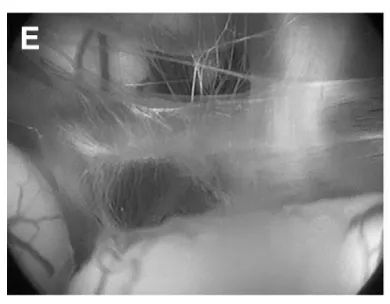

采用先行神经内镜第三脑室造瘘(B-F内镜下视野),再行开颅肿瘤切除的方案,具体过程如下:

(E)经造瘘口窥见基底动脉